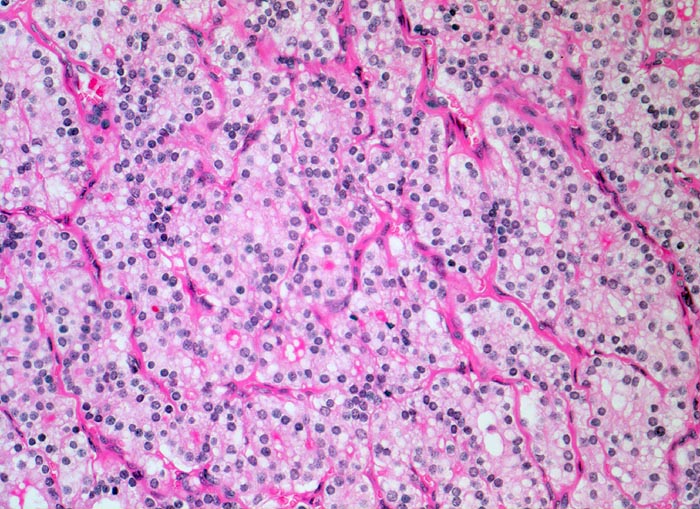

• Kompression des angrenzenden Schilddrüsenparenchyms. Dieses besteht aus grossen Follikeln mit kubischem oder abgeflachtem Epithel und reichlich kompaktem dunklem Kolloid in den Follikellumina.

• Zeichen gesteigerter hormoneller Aktivität im Adenom:

• Kleine Drüsenlumina.

• Teils mehrreihiges kubisches bis zylindrisches Epithel.

• Fehlendes oder nur spärliches helles Kolloid mit zahlreichen Resorptionsvakuolen.